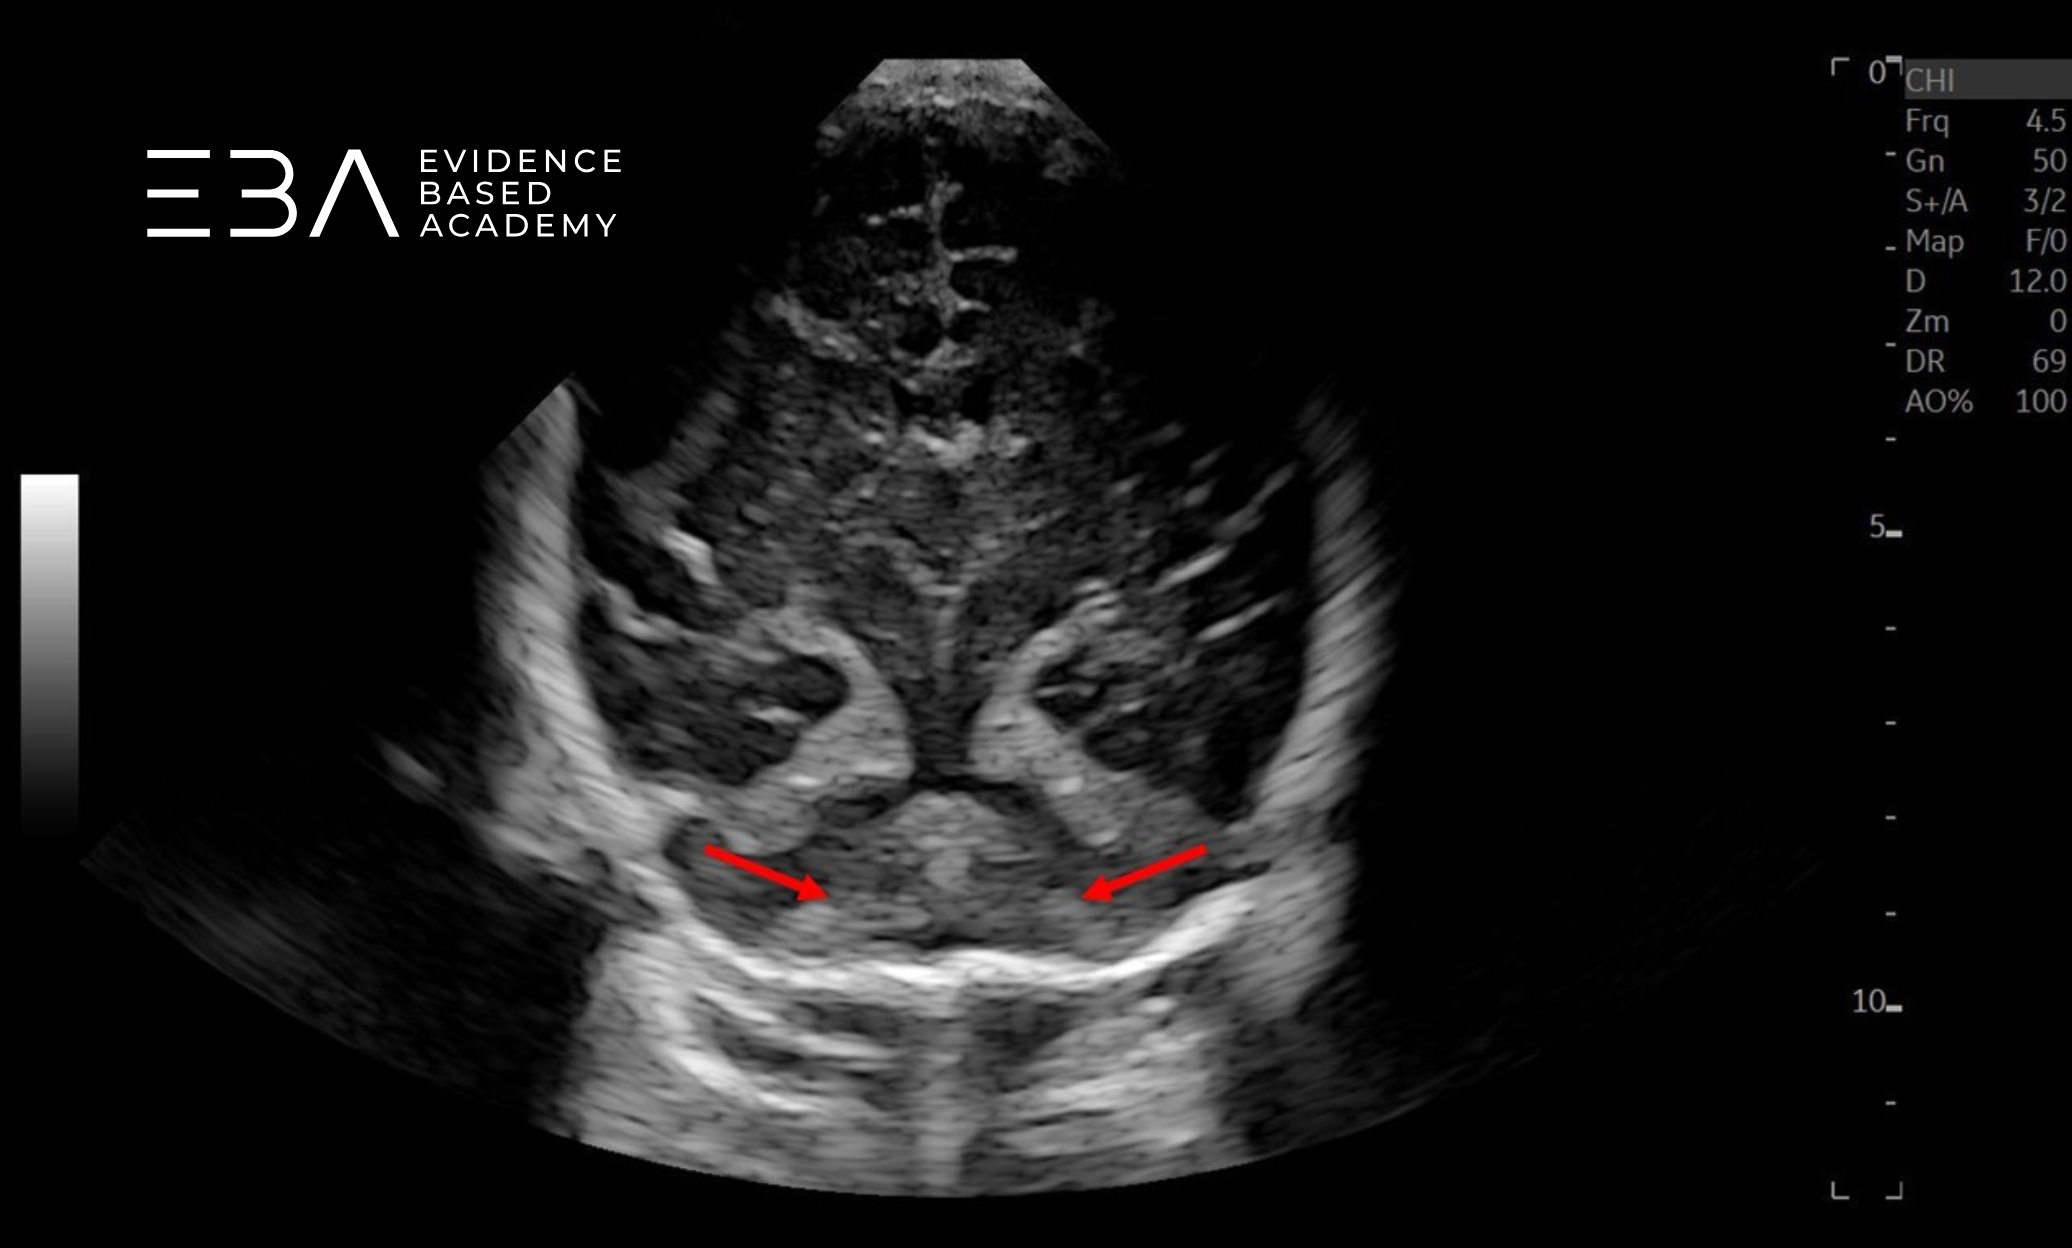

zdj. 1

Głowica mikrokonweksowa. Brak symetrii, wynikającej z nieco skośnego przyłożenia głowicy utrudnia ocenę. Strzałką zaznaczono prawy splot naczyniówkowy.